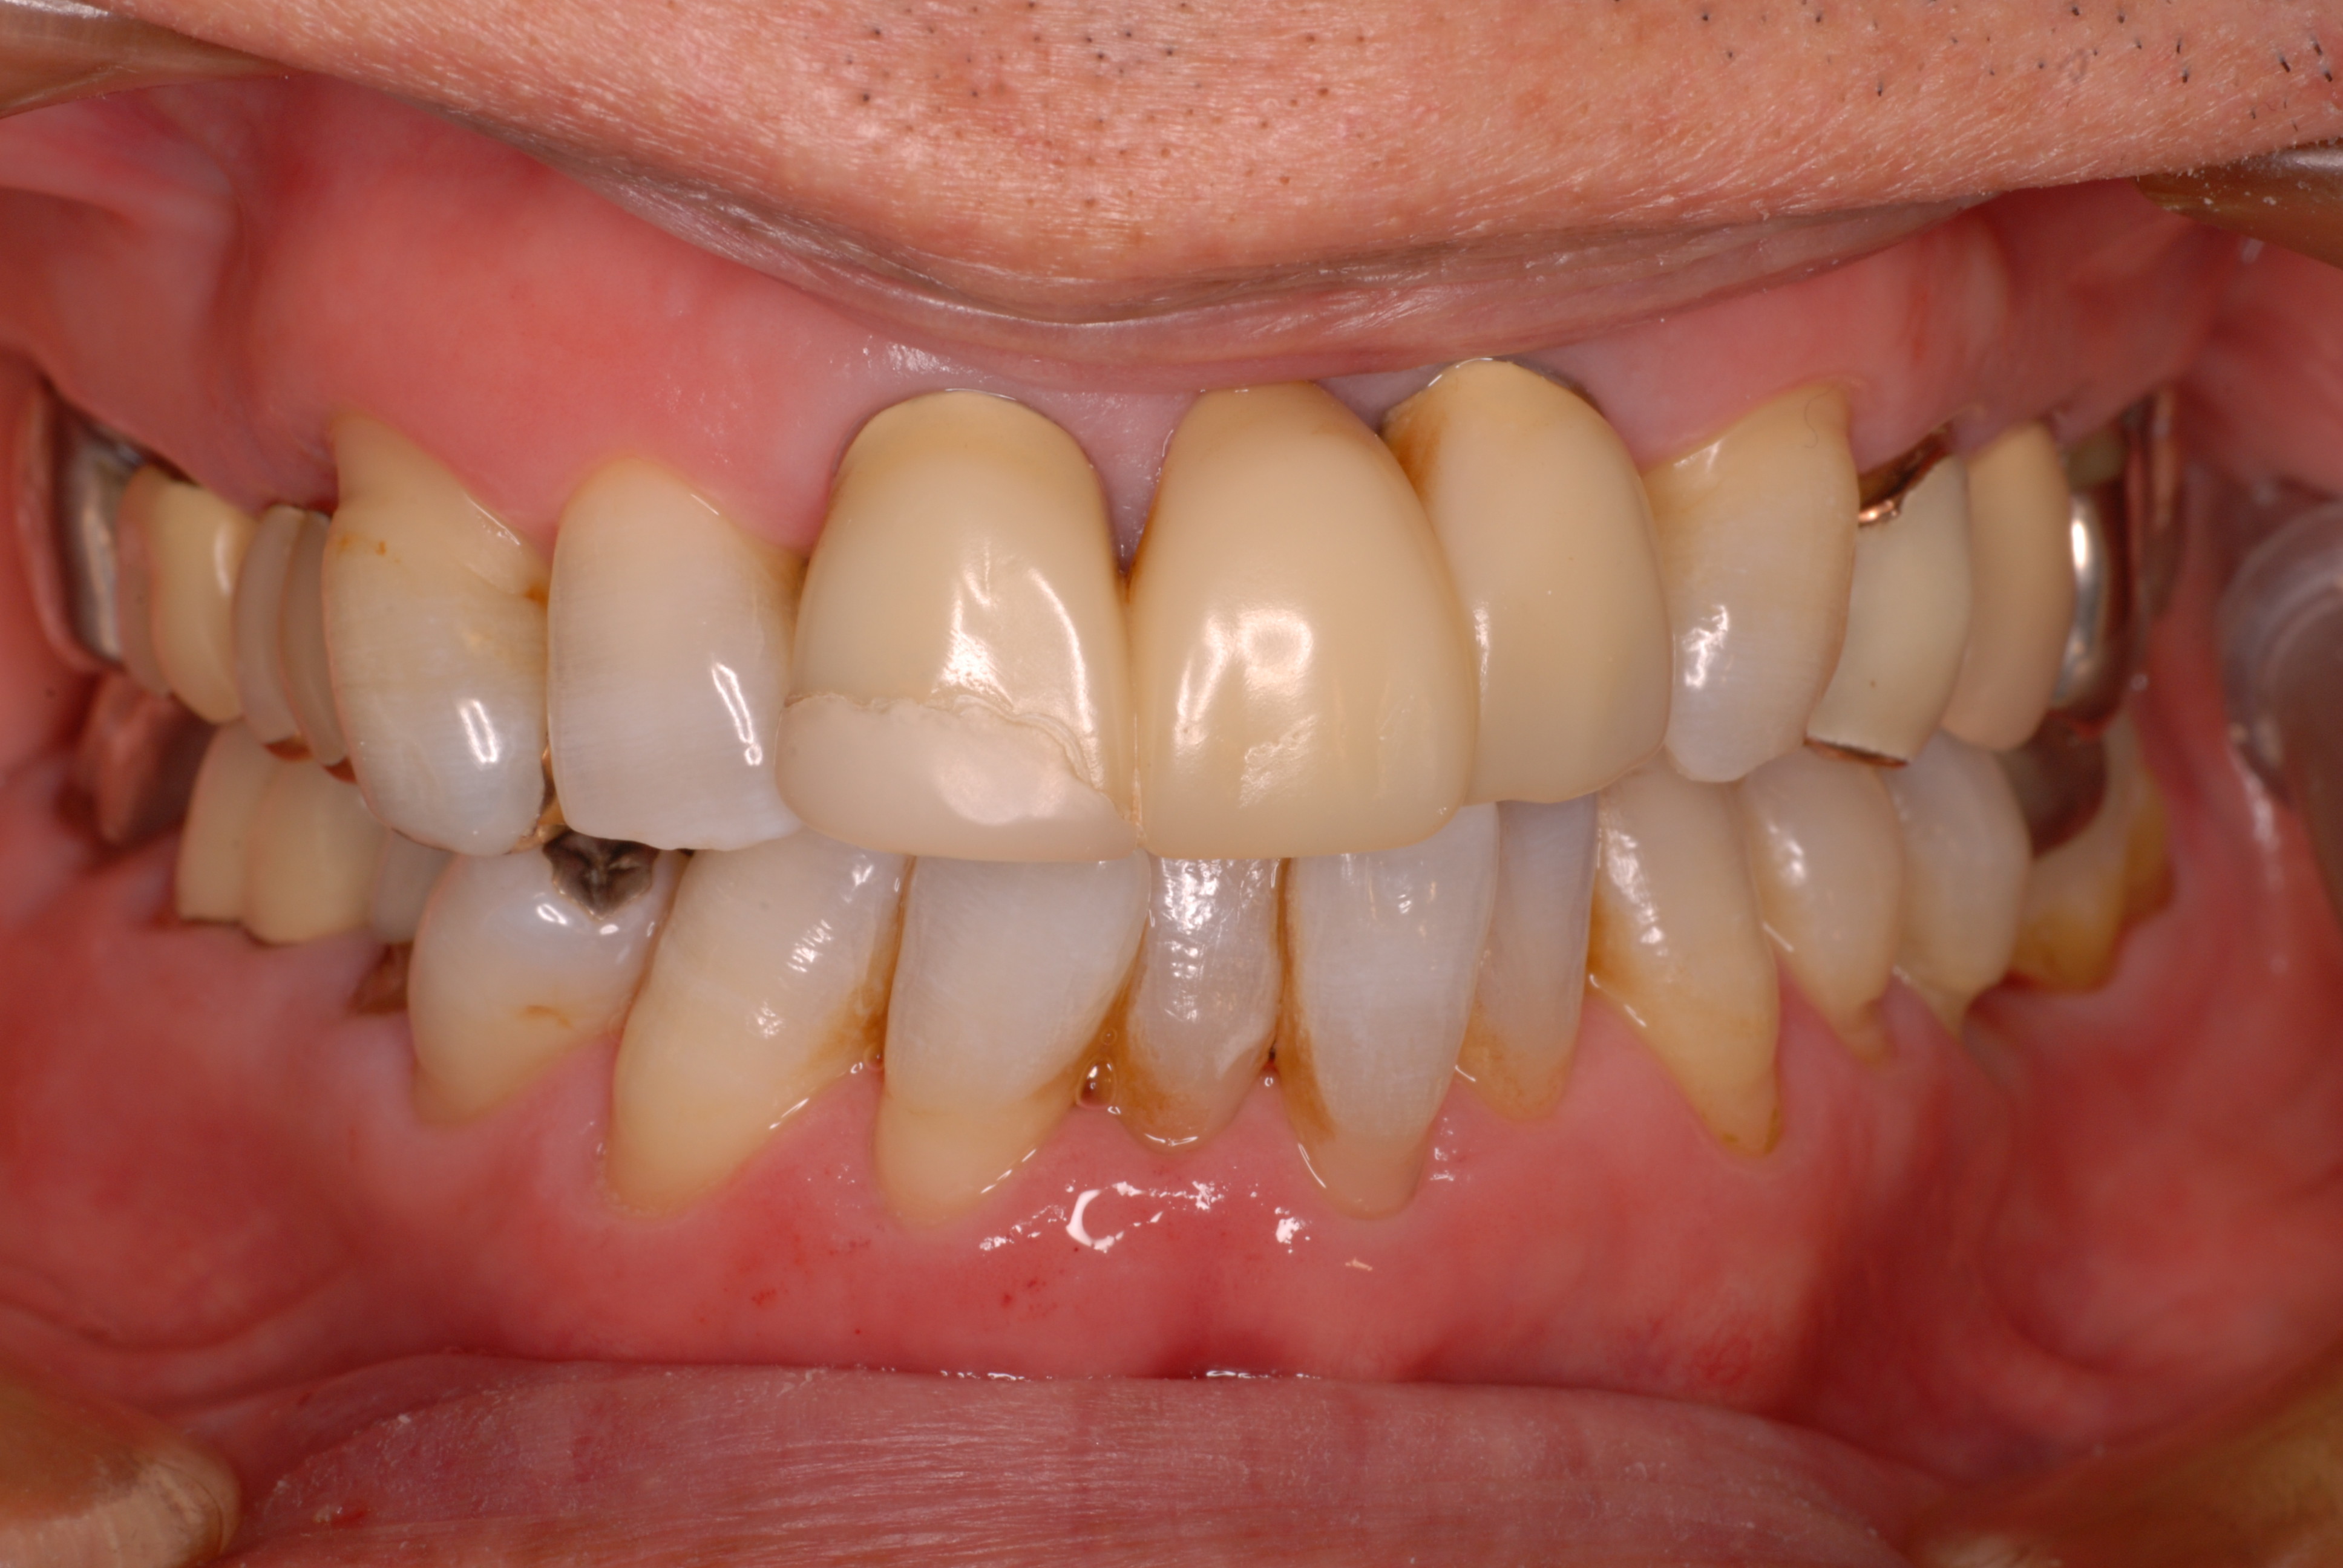

上顎には本人から見て左に一本、右に二本の歯の喪失があり取り外し式の入れ歯を入れていらっしゃいました。

どうにも発音が悪いという事とレントゲンでは右上の歯が捻転(ねじれている)していて形が悪いという事で来院されました。

当時の写真がないのでX線写真と模型を示します。

写真右上の歯が曲がっています。 下の写真の上の歯がありません。

本人では上の左の歯の曲がりを直し、右側は裏側のみ金属にしています。

写真左上の糸切り歯は裏側のみ削っていますから金属ま見えませんね。

平成20年のレントゲン写真です。写真の左上と前の方がつながれています。ゴールドクラウンとプラスチックで見える所はカバーしています。

一部前歯がぶつかって欠けたので2年程前に既成品でカバーしました。それで少し先端が変色しているように見えます。

20年以上たってもびくともしないものなのですね。ブラッシングの重要性を強く感じます。当時はお金がないということで超破格のダンピングで

作製しました。(あ〜安くし過ぎたな〜、笑い)